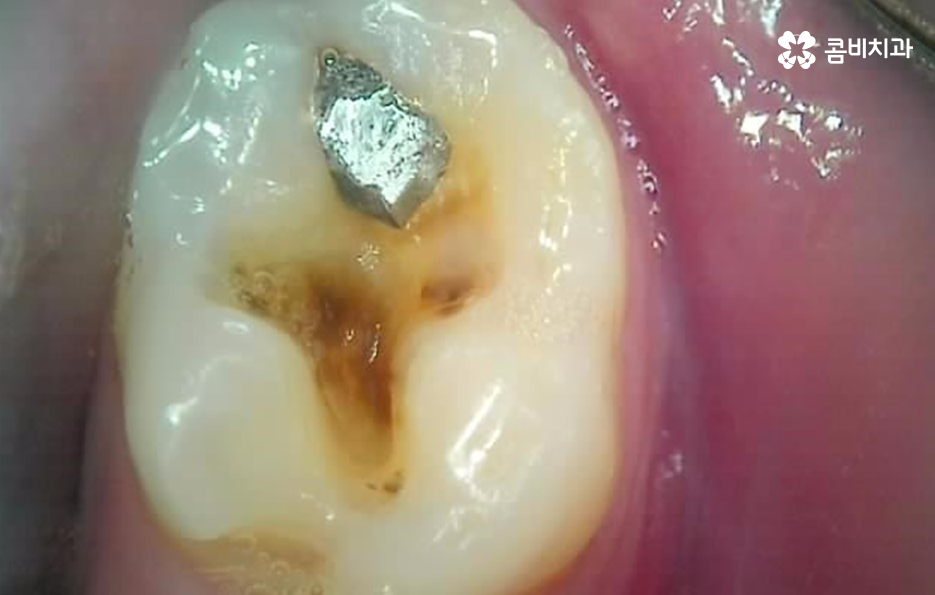

별로 안아팠는데 기존 보철물과 함께 어금니 충치 깨짐이 발생했어요

나이가 들수록 오래된 보철물이 탈락되거나 깨지면서 치아의 손상이 함께 발생되는 사례가 정말 많은데 이러한 문제는 보통 언제 치료를 받았던건지 기억도 안나던 오래된 보철물에서 문제가 발생되는 사례가 많이 있어요

특히 위 환자분의 사례처럼 아말감의 경우에는 빠르고 저렴한 치료 자체는 장점이 있지만 아말감의 특성상 주변 치아가 변색될 우려부터 치아와의 접착이 좀더 빠르게 약해질 우려가 있는 보철물이며 아말감이 조금씩 깨지면서 틈 사이로 충치가 발생되는 사례도 많기 때문에 어금니 충치 깨짐의 경우 보편적으로 보철물 내부에 2차 충치가 발생되면서 치아 내부의 충치가 드러나는 경우가 많고 충치가 없던 경우에는 기존의 치아에 지속적인 마모와 손상이 거듭되다가 치아의 내구성이 약해져서 결국 깨지면서 문제가 드러나는 경우가 많을 거예요